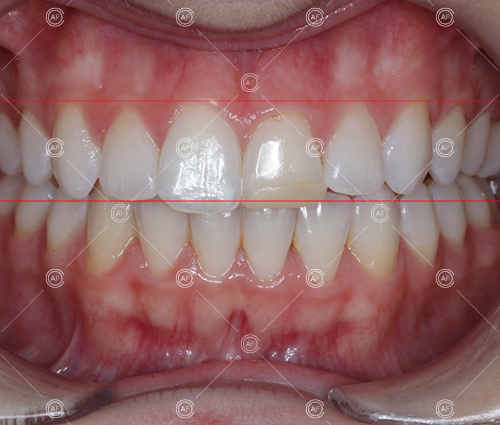

This patient (MH) began her active orthodontic treatment in October 2019 at almost 13 years old. She was unhappy with the appearance of her upper and lower teeth, and especially concerned about the unsightly nature of the high and buccally positioned upper left canine.

about this case…MH presented with class 1 incisors on the class 1 skeletal base with a slightly increased vertical proportion. She had severe crowding in the upper arch and moderate crowding in the lower. Due to the crowding in the lower arch, the lower centre line was off to the left by 2mm.

Buccal segments were essentially class 1 on the right hand side and a full unit class 2 on the left. This is due to buccal exclusion of the upper left 3 and mesial drift of the upper buccal segment.